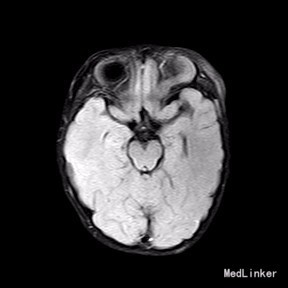

2岁9月患儿,因“左眼睑下垂1年余,头痛、呕吐8天”入院。家属1年前发现患儿左侧眼睑下垂,无法自行张开,一直未予特殊诊治。8天前患者哭闹频繁,诉头痛如爆炸样,剧烈难忍,并出现呕吐胃内容物数次,无伴抽搐、视力下降,无意识障碍。当地医院头颅MRI提示:左侧眼眶扩大,左侧眼球外上方泪腺区见一条状迂曲异常信号影,T1WI呈等信号,T2WI上病灶外缘呈高信号,内为等信号,增强扫描病灶中央呈条状明显强化影,边缘无明显强化,双侧大脑半球对称,灰白质对比正常,未见局灶性信号异常,左侧中颅窝前分蛛网膜下腔增宽,内为脑脊液信号;各脑室、脑池大小、形态均正常,中线结构居中,幕下小脑、脑干无异常,矢状面示垂体大小形态正常,未见局灶性信号异常;增强扫描未见明显异常强化。

完善相关检查,在气管插管麻下行“左额眶部占位病变切除术”。术后病理诊断为“(左眼眶)丛状神经纤维瘤”。术后给予患儿脱水、营养脑神经、抗感染等对症治疗。复查CT未见明显异常。

患儿术后2周左眼睑下垂较术前好转。双侧瞳孔反射、眼球活动均无异常。 丛状神经纤维瘤主要发生于眼睑,在出生后或幼年时期即出现症状和体征。侵袭范围广泛,包括眼睑、眶内软组织、眶骨和邻近的脑、颞部等。眼部最早和最多见为上、下睑软性肥厚,皮下瘤组织增生,使上、下睑隆起。眼睑皮肤常有淡棕色色素斑,眼球向前突出和向下移位。眼球突出虽然很显著,但向眶内纳入并不困难。肿瘤组织可直接侵袭眶内各种结构,上睑提肌首先被波及,引起上睑下垂,上举不足或不能。MRI可准确显示病变的范围尤其显示病变与邻近结构的关系,也可清楚显示其他部位伴发的肿瘤,但难以清晰显示眶壁骨质改变。手术治疗是必要的,手术切除应注意以下问题:1.眼睑病变的切除;2.眶内病变的处理;3.提上睑肌的处理;4.眶骨缺失的处理。丛状型术前诊断容易,但治疗较为棘手,易复发。